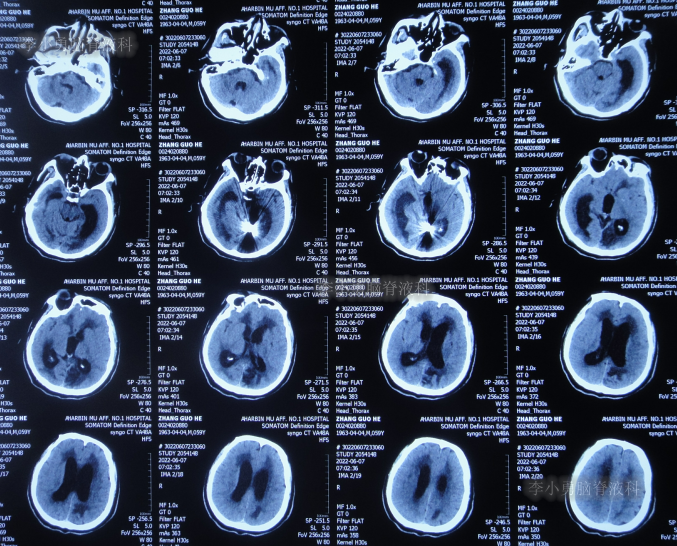

抗感染治疗41天即2022年6月7日,脑脊液化验细菌消失,但查头颅CT示仍脑积水(图-7)。

图-7:2022年6月7日头颅CT

2022年6月8日(第2次住院治疗44天),按计划进行了脑室腹腔分流术。

2022年6月13日(脑室腹腔分流术后5天),术后患者仍走路不稳,有时胡言乱语,言语不清,小便失禁,查头颅CT(图-8)示脑室仍有扩张。

图-8:2022年6月13日头颅CT

2022年6月17日(分流术后9天即第2次该院治疗53天),查头颅CT虽仍有脑积水(图-9),但仍让患者出院,出院时:仍走路不稳,有时胡言乱语,言语不清,小便失禁;转至当地的某医院进行治疗。

图-9:2022年6月17日头颅CT